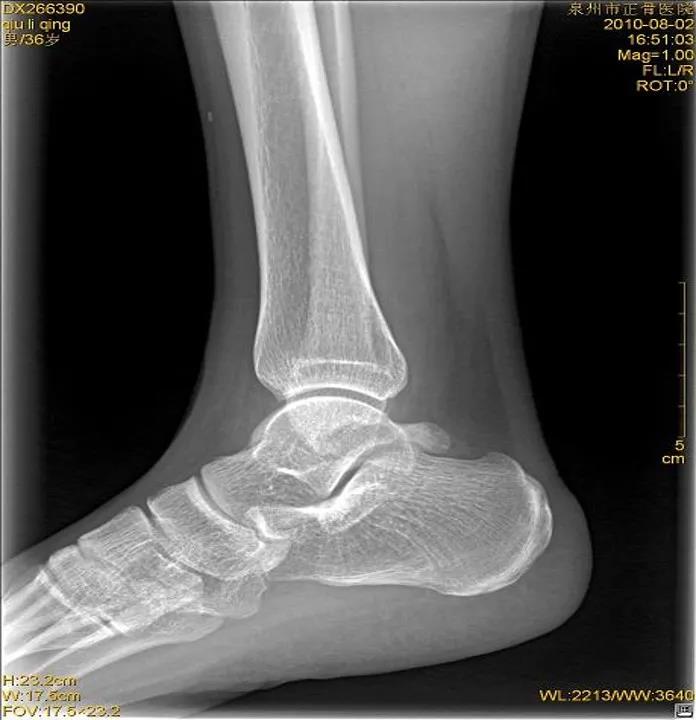

X线片:基本的辅助检查(应注意某些情况并非骨折)CT:能进一步检查隐匿性骨折或撕脱性骨折MRI:可检查肌腱、韧带的损伤肌骨超声:可代替或结合MRI检查软组织的损伤

X线

踝关节正位

踝关节侧位

虽然有所防备,但有时难免发生意外。这时,患者可以先自行评估是否出现关节畸形移位或形成假关节(骨头断裂)等,如果遇到这类严重情况应固定后立即就医,如果只是局部的肿胀瘀斑,疼痛程度较低,就可以先自我急救。伤者在进行急救处理后,如有条件最好在医院进行X线或CT检查,因为小骨头的断裂或撕裂等问题并不会引起强烈的疼痛或肿胀等,但如果没有有效的医疗支具固定可能会致骨折错位或损伤进一步加剧,后期恢复不充分,还会导致陈旧性软组织受伤,在关节尤其负重部位容易引发骨关节病等慢性疾病。